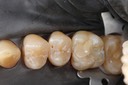

Gary Umeda #18, 19, 20 prep